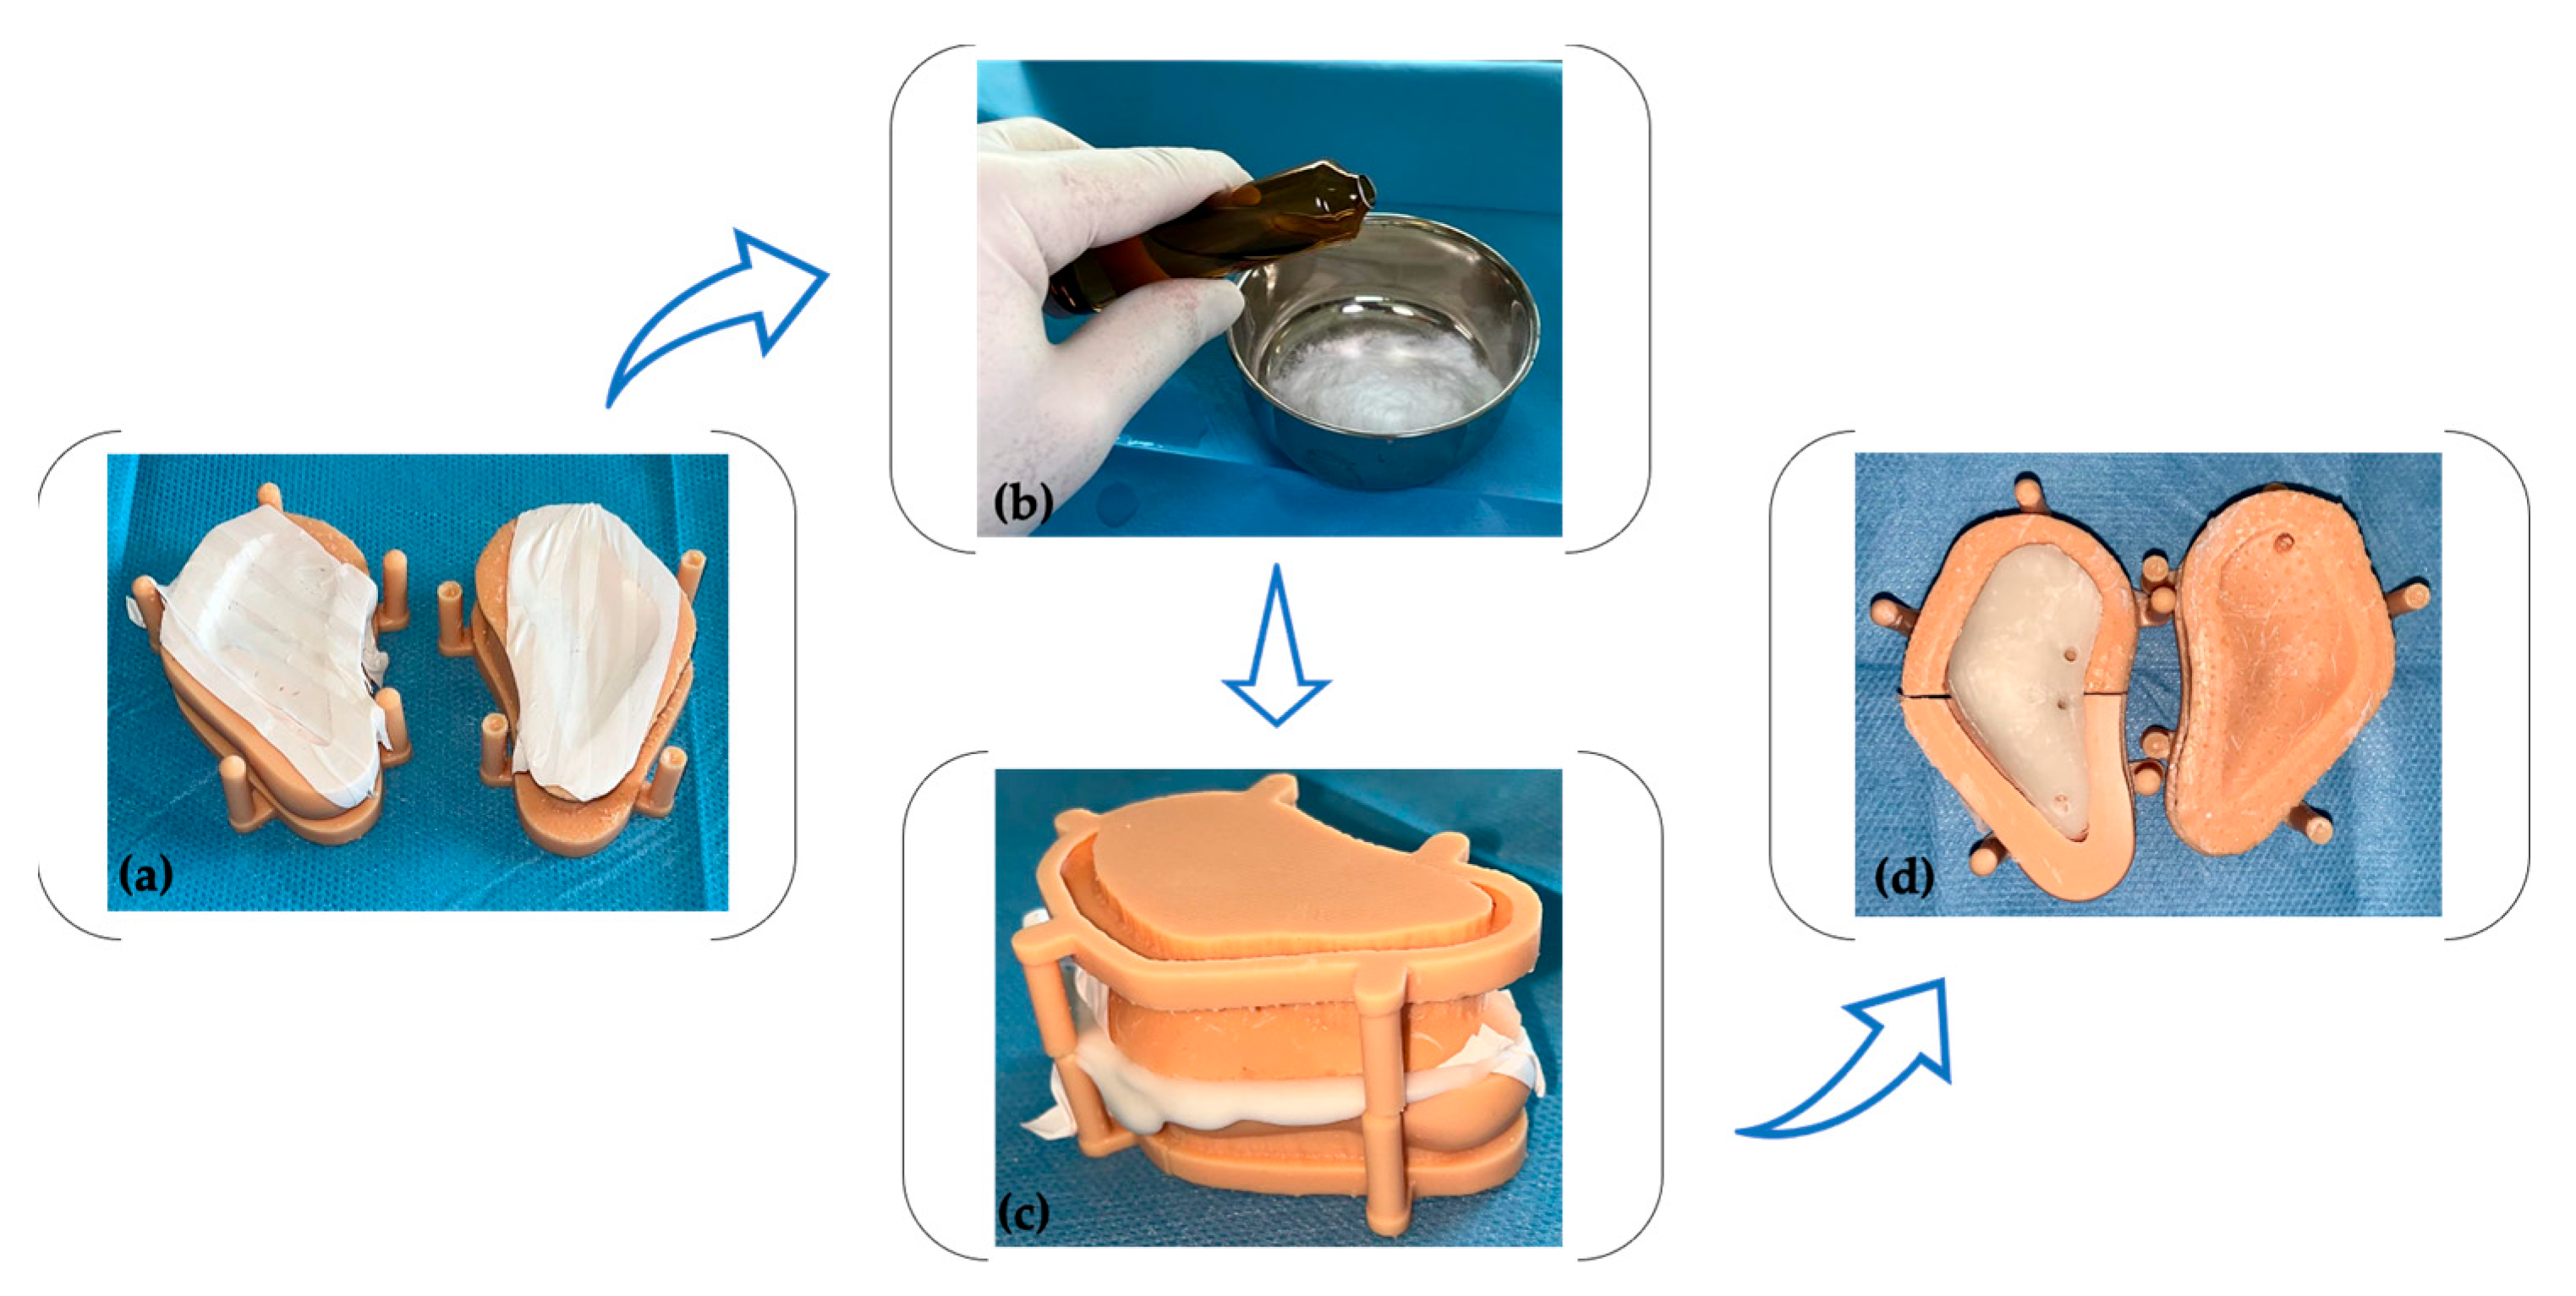

2.1. PSI’s Mold Design and Fabrication